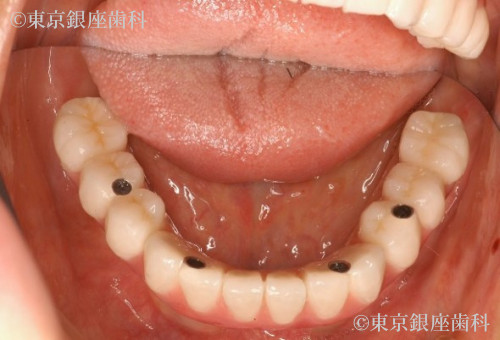

ワンデイインプラントによって全顎的な咬み合わせの再構築と審美の回復が得られることができた症例です。術前は奥歯での咬み合わせの安定が得られなかったため、口腔周囲筋肉の衰えが求められ、表情に張りが認められませんでした。術後は、咬み合わせの安定による、口腔周囲の筋肉の活性化のより表情にはりが戻りました。人口の歯による審美の回復と咬み合わせの安定による、表情筋の活発化と全顎的な口腔機能の回復が得られた症例です。